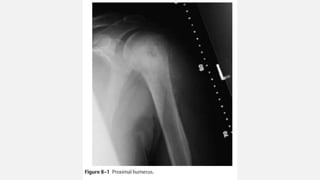

OSTEOSARCOMA PROXIMAL HUMERUS

• A 6-year-old female presents with a 2-month history of pain in her right

shoulder.

• This pain has become increasingly severe, and she is now no longer

using her arm normally.

• X- ray at presentation included a plain film of the humerus.

Orthopedic Oncology by Ernest Conrad